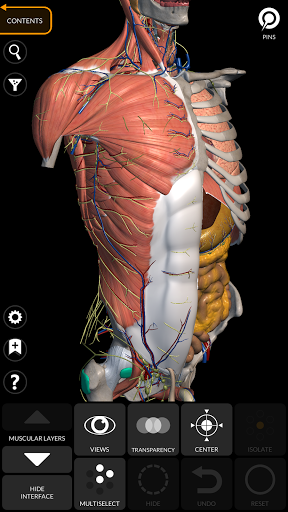

"Anatomy 3D Atlas" vous permet d'étudier l'anatomie humaine de manière simple et interactive.

Grâce à une interface simple et intuitive, il est possible d'observer chaque structure anatomique sous n'importe quel angle.

Les modèles anatomiques 3D sont particulièrement détaillés et avec des textures jusqu'à une résolution de 4k.

La subdivision par régions et les vues prédéfinies facilitent l'observation et l'étude de parties individuelles ou de groupes de systèmes et les relations entre différents organes.

MODÈLES ANATOMIQUES 3D

• Système musculo-squelettique

• Interface simple et intuitive

• Faites pivoter et zoomez chaque modèle dans l'espace 3D

• Option pour masquer ou isoler un ou plusieurs modèles sélectionnés

• Filtrez pour masquer ou afficher chaque système

• Visualisation des muscles à travers des niveaux de couches depuis les plus superficielles jusqu'aux plus profondes